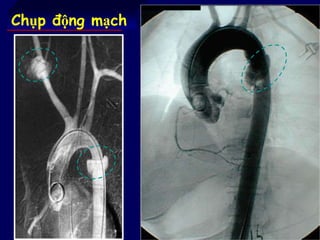

Chụp động mạch

Chẩn đoán hìnhảnh chấn thương động mạch chủ Chụp động mạch chủ CT scan mạch Siêu âm tim qua thực quản Chụp cộng hưởng từ hạt nhân